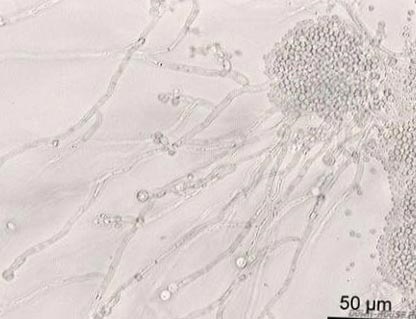

Fig. 4. Bacteriile care populează gura: mutanții Streptococcus (verde). Bakteroides gingivalis, cauzând periodontita (lila). Candida albicus (galben).

Fig. 8. Ciuperci din genul Candida (Candida albicans). Ei în mod constant din momentul nașterii, sunt paraziți pe piele și membranele mucoase, fără a provoca boli. Prin reducerea imunității și utilizarea ineptă a larg spectru antibiotice provoacă infecții fungice la leziuni slab definite la organele interne, pune viața în pericol.